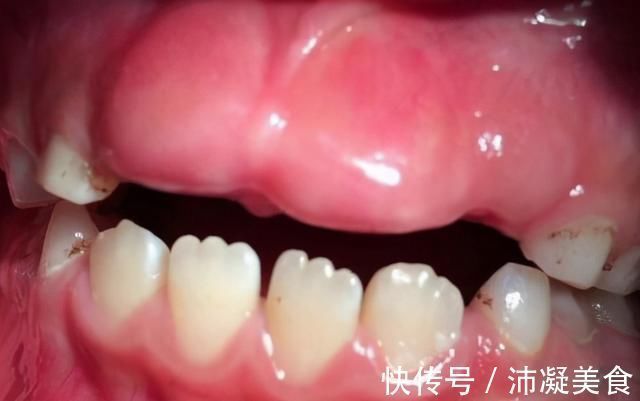

2、牙龈变厚

这是因为乳牙过快的话,牙龈会长期受到咀嚼摩擦变厚,变硬。比如说,本来喜欢的乳牙在7岁的时候会自然掉下来,但是6岁的时候因为摔跤而缺了门上的乳牙。普通的牙齿到7岁为止会发芽。在这一年里,门牙长的地方一直空着。咀嚼食物,将裸露的牙龈摩擦变厚。在牙齿长出来之前,因为牙龈太厚很难硬,所以要把厚的牙龈切开,帮助新的牙齿长出来。这叫做微创开窗助萌术。